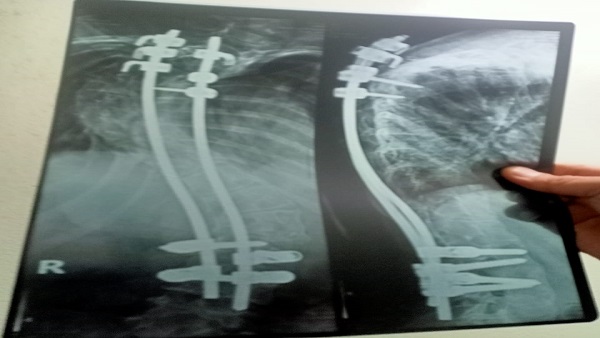

لم تتمكن حنين من الحصول على الدرجة الكاملة فى امتحانات نهاية العام بسبب إجرائها لعمليات جراحية فى العمود الفقرى وحصلت على 278 درجة من 280 حيث فقدت درجتين فقط فى مادة اللغة العربية.

لم تكن الثلاث عمليات التى أجرتهم حنين هي أول الجراحات التى خضعت لها لكنها أجرت قبل ذلك 10 جراحات فى العمود الفقرى منذ ولادتها حتى أخبر الأطباء أسرتها بأنهم فعلوا ما فى إستطاعتهم ولم يعد هناك ما يستطيعون فعله، وأن الأمر بات يتطلب السفر لإجراء عملية جراحية بدولة ألمانيا.

لم يعد لحنين سوى هدفين أولهما السفر لألمانيا لإجراء الجراحة لكى تتمكن من السير على قدميها بشكل طبيعى، والاخر هو التخرج في كلية الطب والتخصص فى جراحة العمود الفقرى حتى تتمكن من تخفيف الام الحالات المماثلة لها.